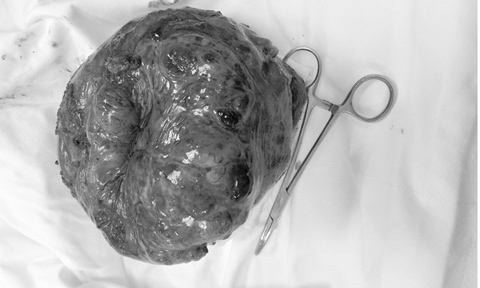

Khoa Ngoại tổng quát BV Nhân dân 115 TP.HCM vừa phẫu thuật bóc tách khối u kích thước 20x12cm, nặng 2kg trong cơ thể bệnh nhân đau dạ dày nhiều năm.

Các bác sĩ BV Nhân dân 115 bóc tách thành công khối u nặng 2kg trong dạ dày bệnh nhân |

Quá trình phẫu thuật, ê-kíp bác sĩ nhận thấy khối u phần đứng bờ cong lớn dạ dày lên đến đáy vị, kích thước u rất to, khoảng 20x12 cm.

U viêm dính vào cơ hoành, dính vào mặt trước tụy, dính chặt vào cuống lách và đuôi tụy nên tiến hành gỡ dính u ra khỏi các cơ quan này.

BS Huy cho biết, người bệnh bị u Gist (Gastrointestinal Stromal Tumor) của dạ dày - một loại u trung mô của đường tiêu hóa, chiếm khoảng 1 - 3% các loại u của đường tiêu hóa.